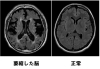

脳萎縮や脳虚血などMRIによって頭の中の状態を確認できます「ビハーラ花の里病院」

脳萎縮や脳虚血などMRIによって頭の中の状態を確認できます

脳・脊髄・末梢神経・筋肉の障害によって起こる様々な病気を専門とする診療科で、頭痛やめまいのような身近にみられる病状から、突然の意識障害や麻痺といった救急疾患まで、さまざまな症状が対象になります。

血液検査やレントゲン検査などの他に、頭部CTやMRIといった画像検査、脳波や末梢神経伝導検査といった電気生理学的検査なども行い診断・診療を行います。